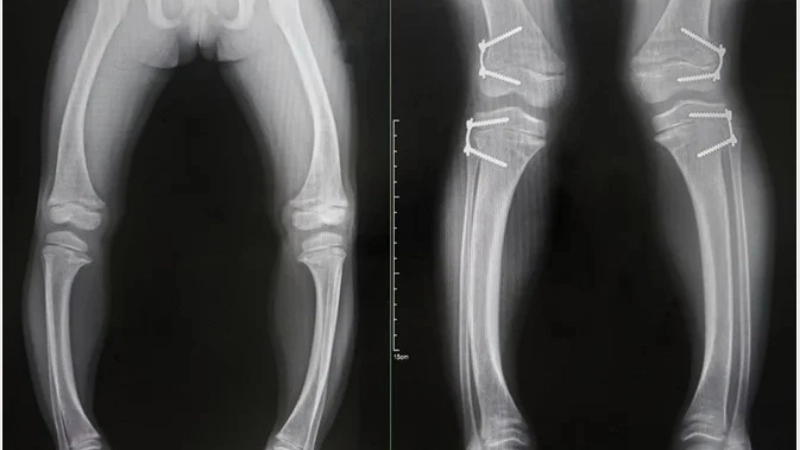

Hình ảnh X-quang biến dạng xương do còi xương

Dấu hiệu trẻ bị còi xương chân vòng kiềng

• Khi bệnh tiến triển, sẽ xuất hiện các biến dạng ở xương như thóp lâu liền, đầu bẹp, lồng ngực dô (ngực gà), chân vòng kiềng, làm cho trẻ còi xương chậm lớn.